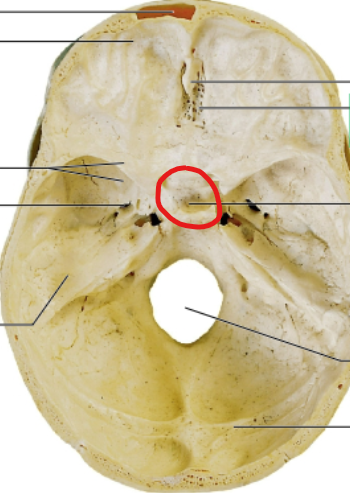

sella turcica

pituitary gland sits here

cribriform plate

olfactory nerves sits here